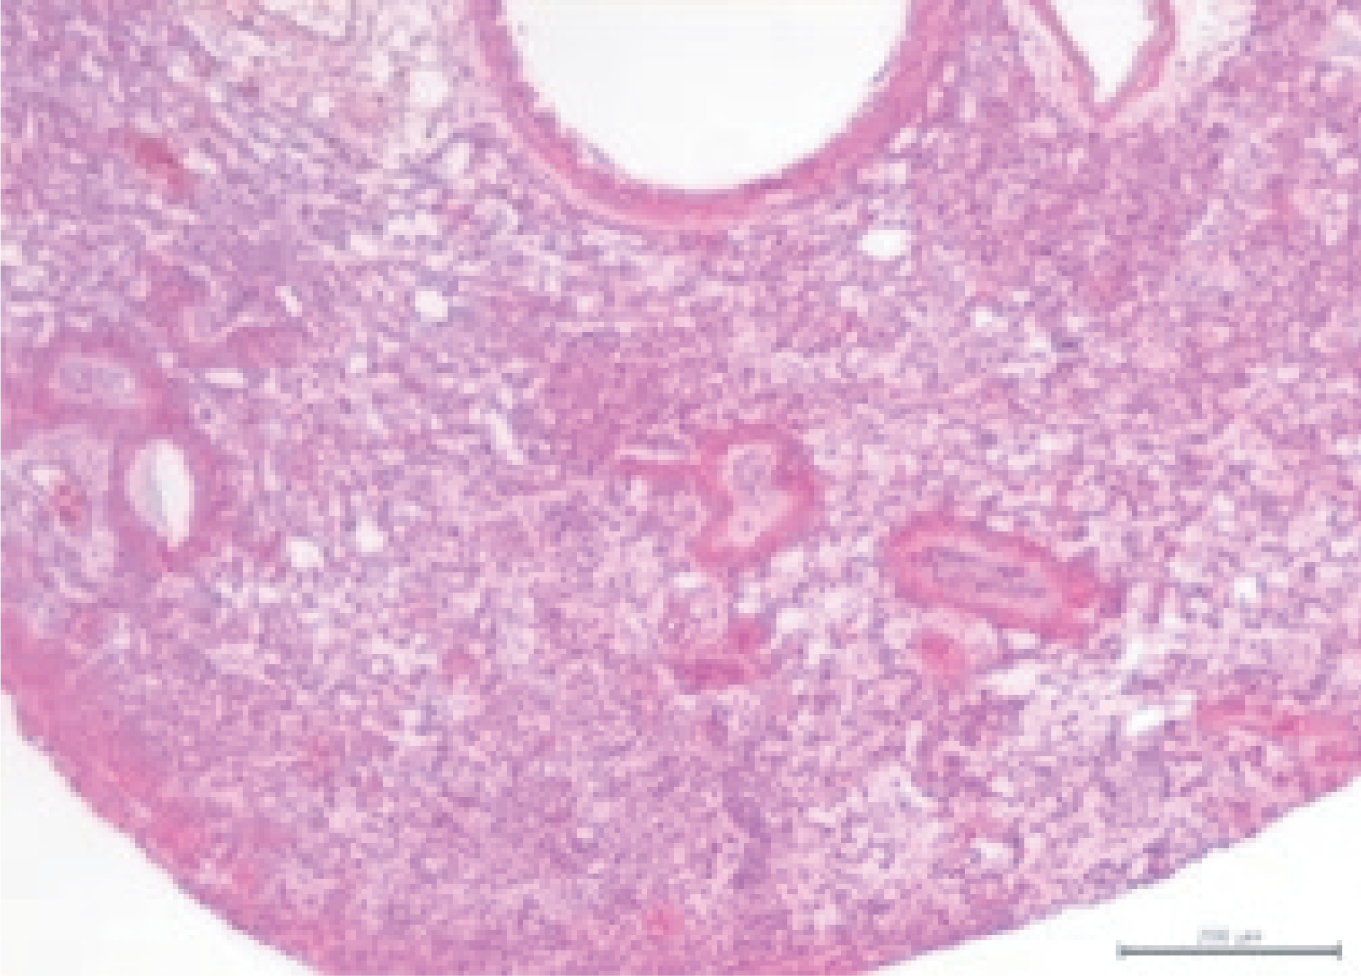

Pathological Criteria:

The lungs of model animals primarily exhibit interstitial inflammation, characterized by inflammatory cells and serous exudate in the interstitium surrounding alveolar walls, blood vessels, and bronchioles. A large amount of inflammatory serous fluid and inflammatory cells, predominantly macrophages, are also visible in the alveolar spaces.

Lung of Model Group: Marked interstitial pneumonia with alveolar serous exudation and minimal perivascular inflammatory cell infiltration